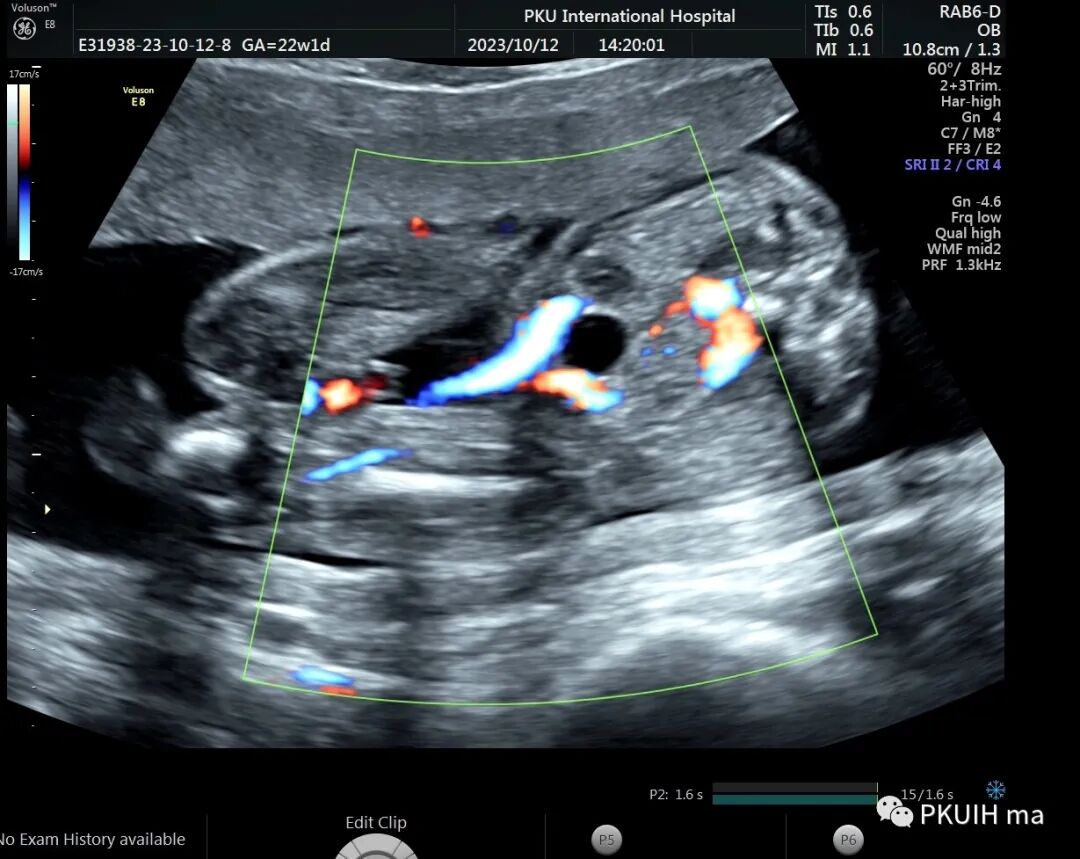

右肾大小位置正常,右肾动脉可见,左肾动脉缺如,正常的左肾区未见肾组织回声,可见肾上腺平卧。于膀胱后上方见一肾组织回声,大小约1.5x1.4x1.0cm,皮髓质分界欠清晰,血供来源于髂动脉。